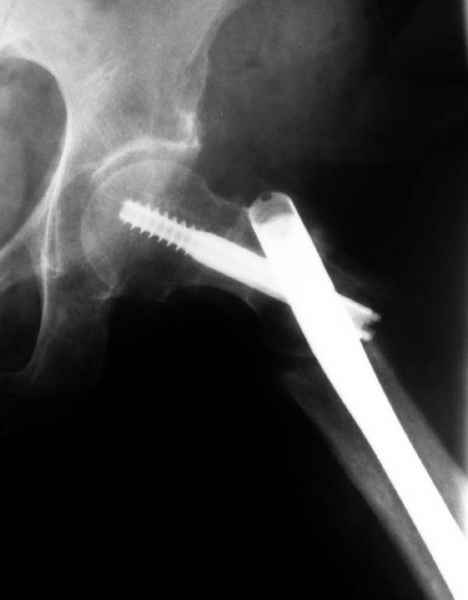

77 летняя больная направлена в нашу клинику на дальнейшее лечение. Из истории, травму получила в сентябре 2007 года и по поводу перелома шейки бедра больная была проперирована тремя каннюлированными шурупами с явным нарушением технологии установки шурупов. Внизу вместо одного шурупа имеется два, что привело к стрессу латерального кортекса. Через месяц по поводу ятрогенного подвертельного перелома сделана фиксация длинной Гамма 3. Установлен без проксимальной блокировки? (set screw). В данный момент имеется несостоятельность конструкции и ложный сустав. Передвигается с помошью костылей, конечность укорочена на 2 см. Какие будут рекомендации?Djoldas Kuldjanov, MDDepartment of Orthopedic SurgerySt. Louis University Medical Center

Видимо, проблем тут две: во-1-х, центральный отломок был оставлен в варусно-сгибательной установке, во-2-х, не динамизировали вовремя.

Нижние винты хотели сломаться, но, увы, один не сломался, и тогда сломался гвоздь. Хотя и при динамизации в таком положении отломков

могло не срастись.